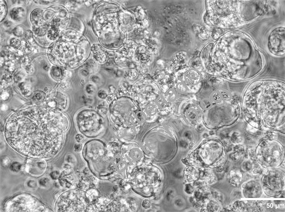

上海中医药大学汤忞研究员以“生物3D打印和生物材料用于肿瘤模型构建与调控机制研究”为题进行报告,介绍了通过生物3D打印构建高仿生肿瘤微环境模型的新进展。该技术可模拟细胞间相互作用机制,用于药物敏感性预测和联合用药评价,为肿瘤基础研究、临床应用及新药研发提供更具临床相关性的工具

在肿瘤相关领域,赛箔与合作者共同研发基于生物3D打印技术构建的肿瘤微组织(PDT),涵盖十余个癌种,包括高发肿瘤、难治肿瘤、妇科肿瘤和儿童肿瘤,培养成功率超过了90%。通过近千例样本研究,证实PDT与患者组织具有高度一致的分子特征和药物敏感性,1-2周即可获得准确的药敏检测结果,为治疗赢取宝贵时间,并且可为新药研发企业提供药效评价、入组标准建立、适应症筛选等服务。在再生相关领域,赛箔已建立多种3D组织工程皮肤,包括表皮模型、全层皮肤模型、黑素皮肤模型等,并相应开发多种体外功效测试方法。